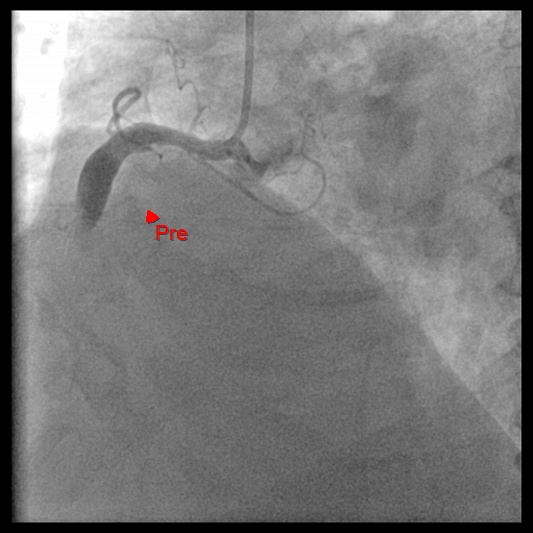

In 2023, prior to the current admission, the patient was hospitalized for percutaneous coronary intervention (PCI) due to coronary artery disease. At that time, CAG revealed total occlusion of the mid-RCA. Consequently, plain old balloon angioplasty and stenting with a Resolute Onyx™ drug-eluting stent (4.5 mm × 30 mm; Medtronic, USA) were performed to the distal RCA and posterior descending artery. Additionally, ectasia of the left circumflex artery and RCA was observed.

Relevant Catheterization Findings

Access via a 7 Fr in 6 Glidesheath Slender (Terumo, Japan) in the right radial snuffbox. CAG revealed total mid-RCA occlusion. Intracoronary Tirofiban was given. A Sion Blue ES wire (ASAHI, Japan) reached the distal RCA. Aspiration with Thrombuster II and ST01 catheters removed minimal debris. Thrombus fragmentation with Ryurei and Accuforce balloons and Pronto V4 achieved TIMI 2 flow, but thrombus persisted. The patient received Enoxaparin, dual antiplatelets, and Tirofiban infusion for 3 days.